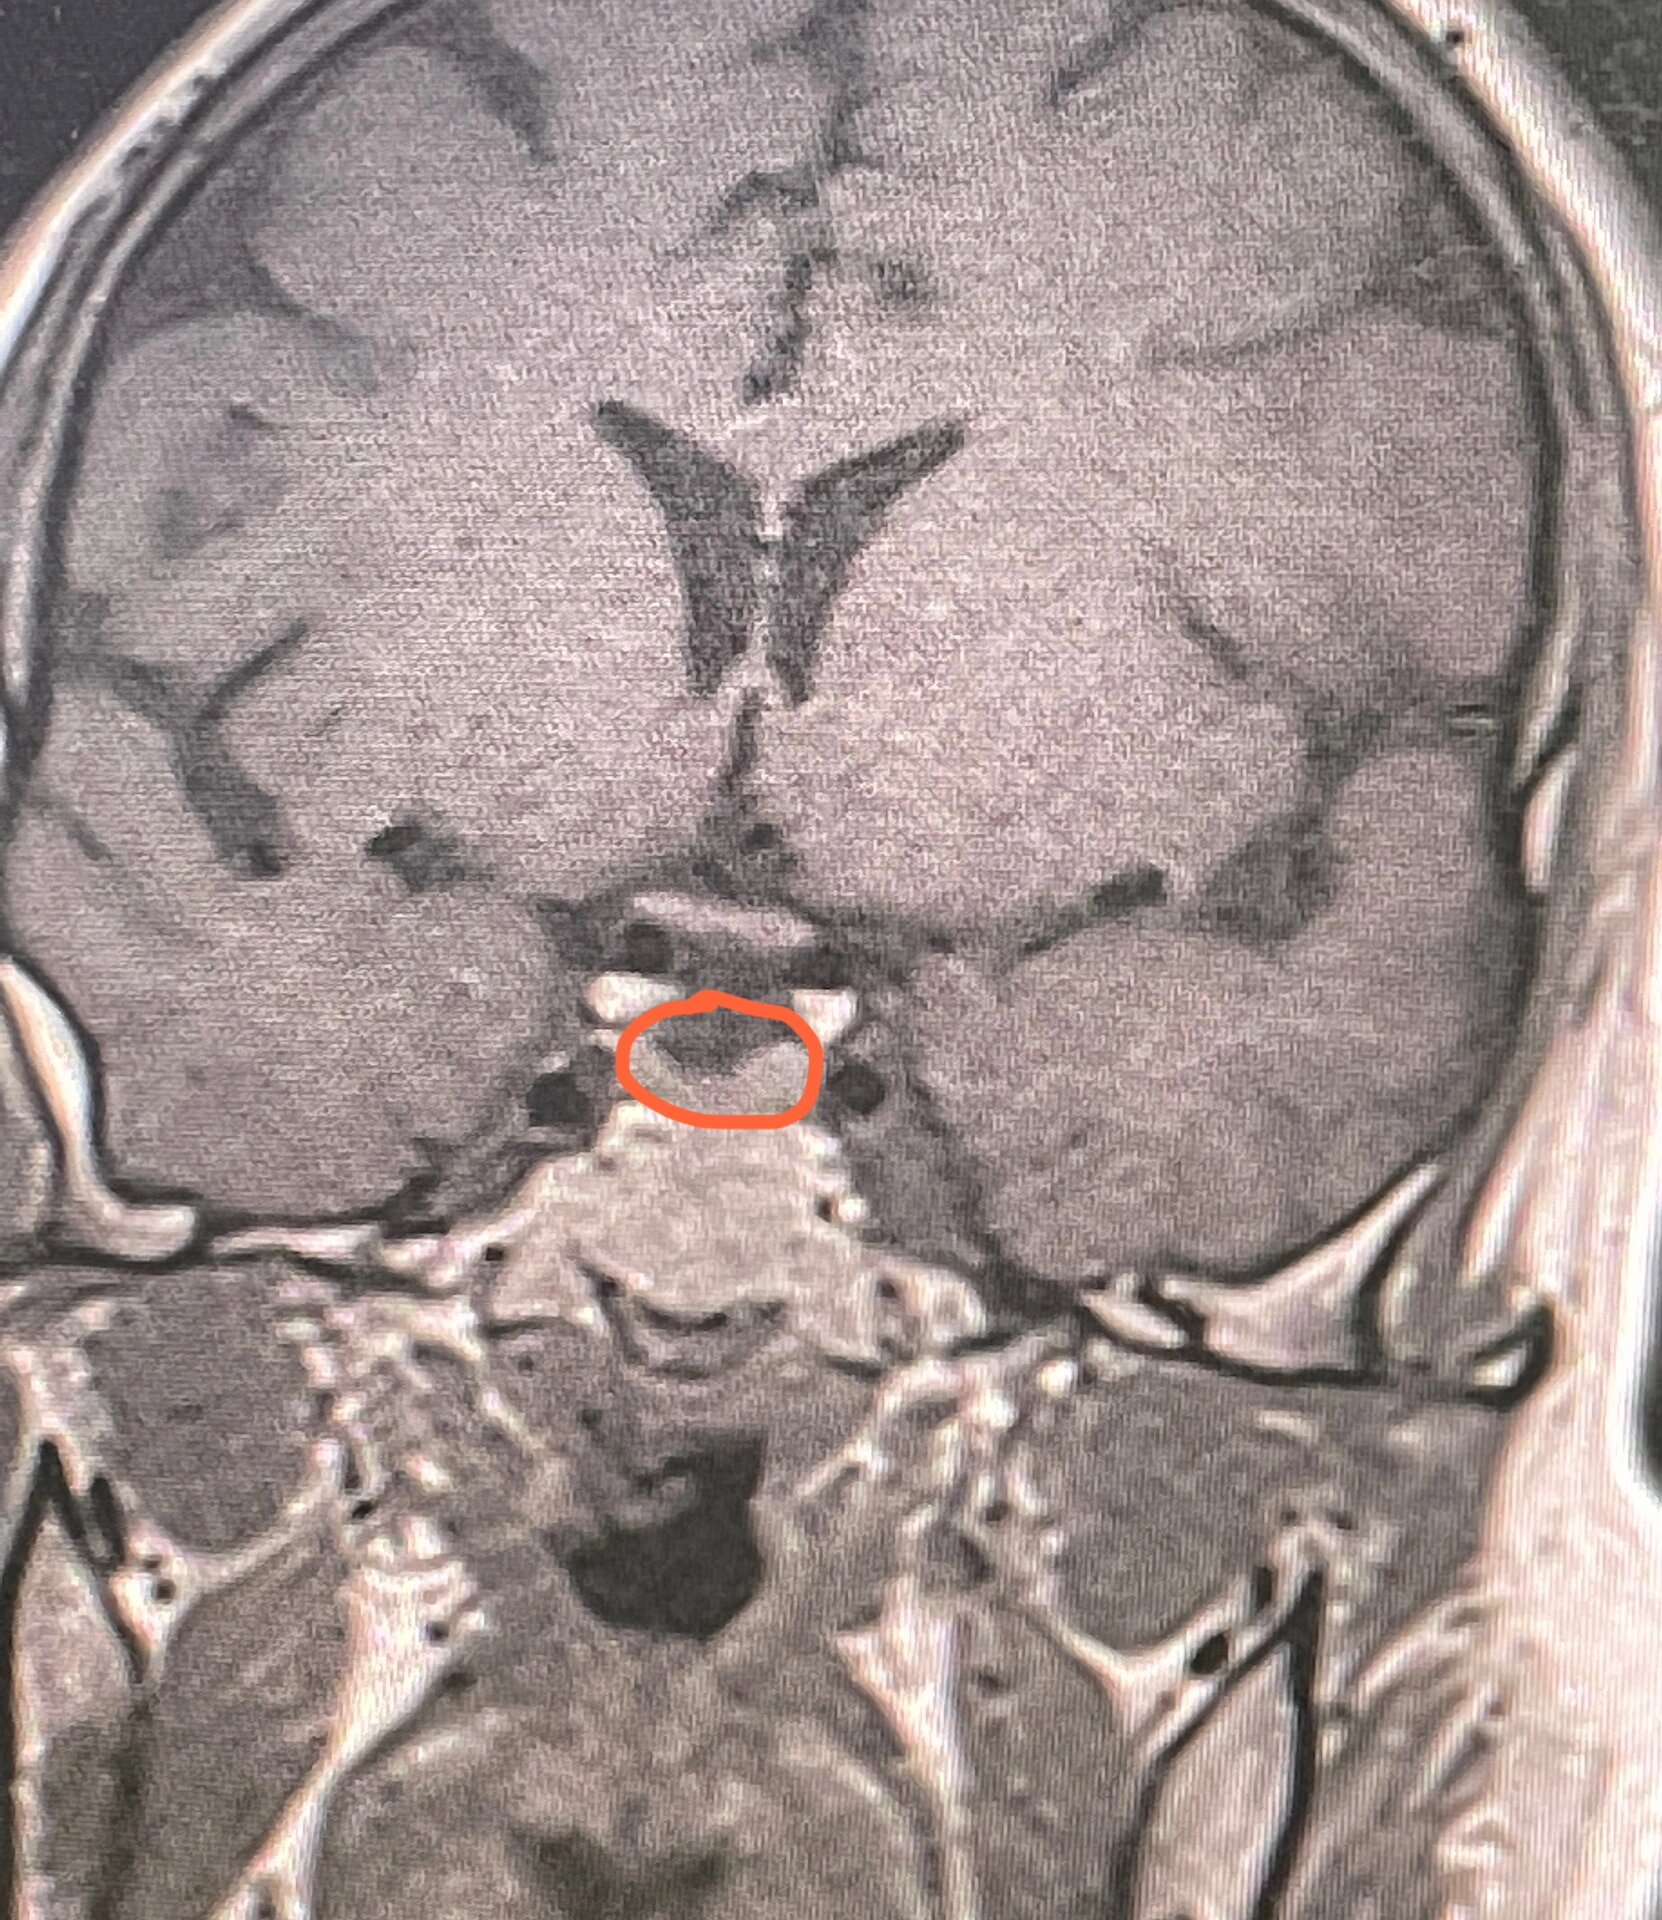

视觉通路,垂体,中线结构异常,什么综合征?